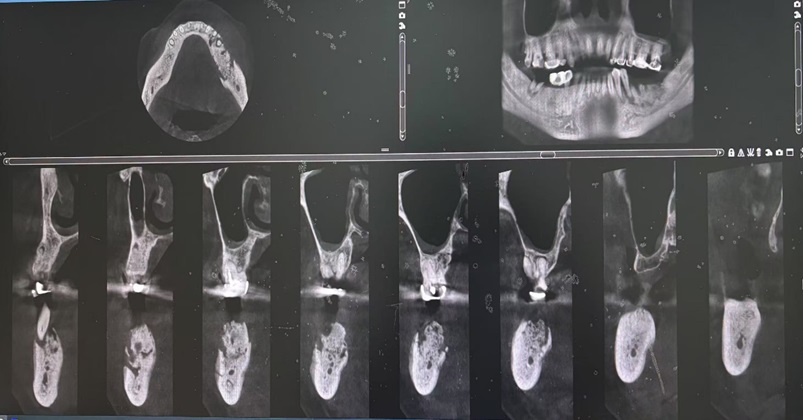

(MRONJ患者的影像资料 图片由作者提供)

防范和降低手术风险的基础是对疾病的早期诊断,MRONJ的早期诊断与分期仅靠医生主观判断相对困难,虽然组织病理学检查是支持临床诊断的重要依据,但考虑到此类患者术后创口愈合能力较差,一般情况下并不建议做活组织检查。而影像学表现随MRONJ不同阶段表现各异,能较客观描述其严重程度,对于评估颌骨坏死的程度具有重要的参考意义,可为治疗方案的科学制定提供指导。